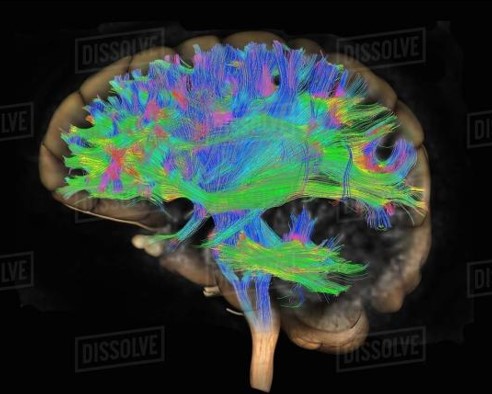

核磁共振成像具有丰富的成像序列和功能发展潜力,这方面至今仍然是非常活跃的研究和应用领域,例如可以通过巧妙的安排成像序列和射频磁场的作用方式来刻画大脑白质,神经纤维的聚集和链接特性,这一成像技术被称为磁共振弥散张量成像技术 (Diffusion Tensor Imaging,DTI), 在科学研究和医疗诊断上有广泛的应用。

图9. 磁共振弥散张量成像形成的大脑纤维追踪

此外,fMRI与弥散张量成像 (DTI) 和我们之前介绍的脑磁图 (MEG),经颅磁刺激 (TMS) 等技术相结合,可得到更多的脑功能活动信息。弥散张量成像可在三维空间内定量分析,无创跟踪脑白质纤维束,fMRI与弥散张量成像技术可以建立激活区域的功能连接网络图,有利于解释结构与功能之间的关系。脑磁图反映神经细胞在不同功能状态下产生的磁场变化,可以提供脑功能的即时信息和组织定位,fMRI与脑磁图技术相结合可以弥补其时间分辨率的不足,可解决脑区域性活动的时间问题;经颅磁刺激可以无创地在皮层产生可传导性电流,从而对刺激位点或有突触联系的皮层兴奋性产生抑制或易化,通过整合fMRI的结果,可以应用于脑损伤和其它疾病的功能神经外科手术。随着fMRI和图像后处理技术的不断改进和完善、高磁场强度MRI的发展,能够使fMRI试验的可重复性和空间定位的准确性大大提高,在脑神经科学、认知和心理等方面的临床和基础研究中的应用将更加深入与广泛。